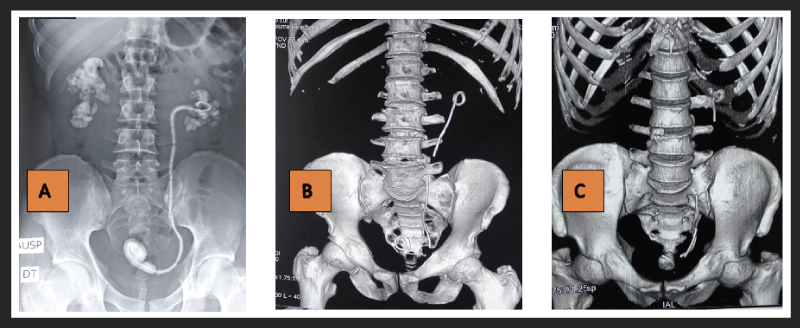

The main indication for JJ stent was lithiasis, as shown in (Table 1). JJ stent was unilateral in 33 patients (14 on the right and 19 on the left) and bilateral in 6. The mean duration of JJ stent use was 11 months (range: 4 months to 5 years).  Complications were either infectious or mechanical. Infectious complications were the main reason for hospitalization. Infectious complications were dominated by multidrug-resistant urinary tract infections, and mechanical complications by calcifications of the double J stent. Figure 1 and Figure 2 show an iconography of complications and intraoperative images.

Figure 2: A: Extraction of calcified JJ after open surgery (lumbotomy pyelotomy); B: View of calcified proximal loop of the during percutaneous nephrolithotomy with lithoclast; C: Endoscopic view of calcified distal loop of JJ. View Figure 2